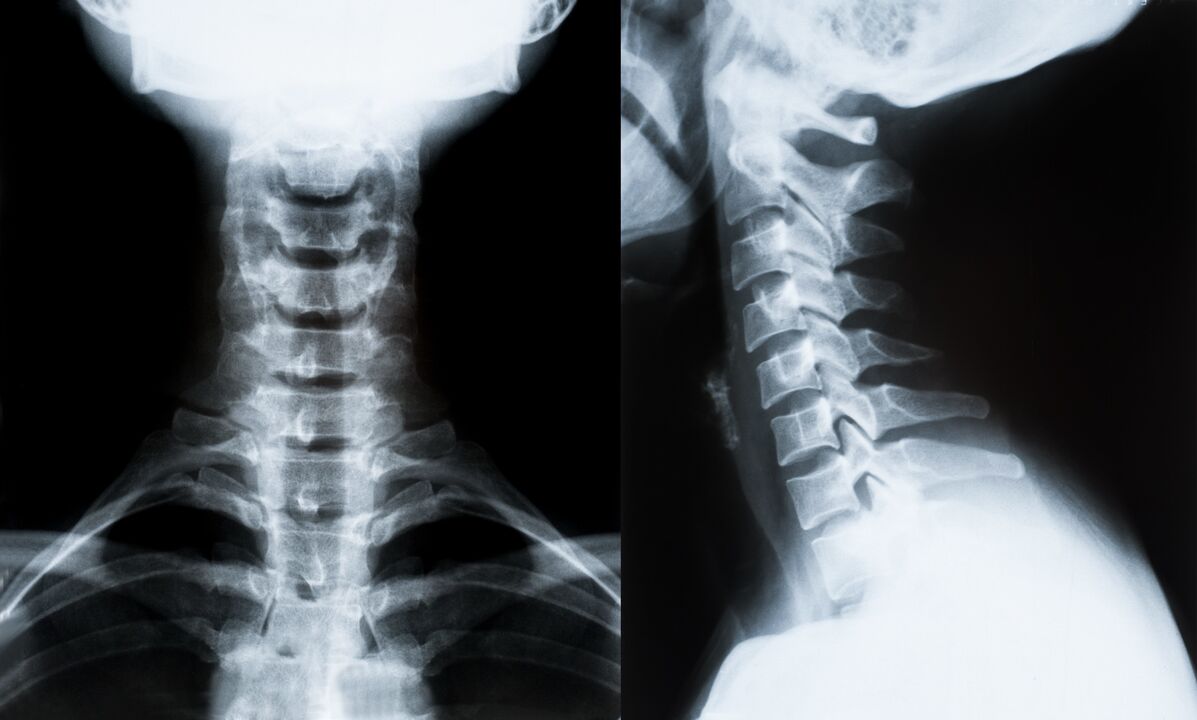

Galvenās mugurkaula kakla daļas osteohondrozes diagnostikas un turpmākās ārstēšanas noteikšanas metodes:

- Rentgens. Vismazāk efektīva, bet tradicionālā diagnostikas metode.

- Magnētiskās rezonanses attēlveidošana ir visefektīvākā diagnostikas metode. Ar šāda veida pacienta izmeklēšanu ir redzamas visas nepieciešamās struktūras.

- Ja nepieciešams izmērīt izmaiņas, tiek izmantota datortomogrāfija. Nosaka trūču un citu lietu klātbūtni.

- Pēdējā metode ir ultraskaņas dupleksā skenēšana. Šī pētījuma metode nosaka asinsrites ātrumu artērijās.

Mājās nav iespējams precīzi noteikt mugurkaula slimību.